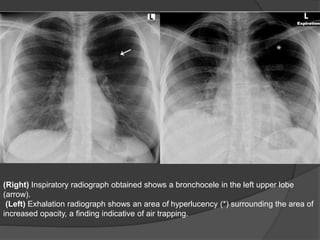

CECT

o Central, low to intermediate attenuation, rounded or branching tubular mass

o Hyperinflated distal lung with decreased vascularity

• HRCT: Air-trapping confirmed in hyperlucent distal lung on expiratory images.

(Left) Axial CECT shows a rounded lesion centrally adjacent to the right upper lobe

bronchus (open arrow). The distal lung is hyperlucent with decrease in pulmonary

vascularity (arrow).

(Right) Axial CECT shows branching tubular structure in the left upper lobe (open

arrows). Distal to these dilated fluid filled bronchi is hyperlucent lung with decreased

vascularity (arrows).

(Right) Inspiratory radiograph obtained shows a bronchocele in the left upper lobe

(arrow).

(Left) Exhalation radiograph shows an area of hyperlucency (*) surrounding the area of

increased opacity, a finding indicative of air trapping.